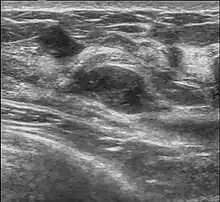

A fibroadenoma is usually diagnosed through clinical examination, ultrasound or mammography, and often a biopsy sample of the lump.[9] Suspicious findings on imaging may result in a person needing a biopsy in order to gain a definitive diagnosis. There are three types of biopsies: fine-needle aspiration, core-needle biopsy and surgical biopsy. The method of biopsy depends on the appearance, size and location of the breast mass.[10]

Macroscopic

Approximately 90% of fibroadenomas are less than 3 cm in diameter. However, these tumors have the potential to grow reaching a remarkable size, particularly in young individuals. The tumor is round or ovoid, elastic, and nodular, and has a smooth surface. The cut surface usually appears homogenous and firm, and is grey-white or tan in colour. The pericanalicular type (hard) has a whorly appearance with a complete capsule, while the intracanalicular type (soft) has an incomplete capsule.[11]